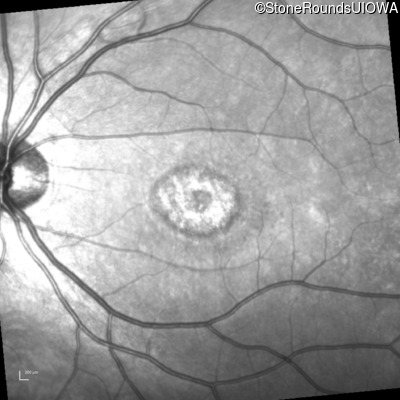

Infrared Fundus Photograph - Right - 20/50 -1

Exemplar

Infrared Fundus Photograph - Left - 20/50 +2